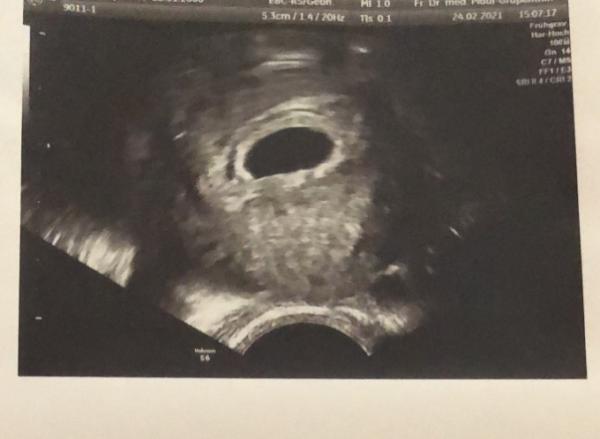

Hey ihr Lieben, Ich war eben im Krankenhaus, weil ich die letzten Tage so unangenehmes Ziehen im unterleib hatte(nur abends) Jetzt haben die mich untersucht laut letzter Periode soll ich bei 5+5ssw sein und es ist nur eine mini fruchthöhle zu sehen. Sie sagten mir außerdem das ich ein kleines hämatom von 1,4cm habe und das es abbluten muss. Die gehen von einer Fehlgeburt aus können es aber nicht 100% sagen, es könnte auch sein das die Schwangerschaft noch nich so weit fortgeschritten ist. Jetzt habe ich einen Clearblue mit wochenbestimmung gemacht der zeigt 2-3 an das bedeutet 4-5 Woche und in der Woche ist es normal das man nur eine kleine Fruchthöhle sieht, was meint ihr, kann ich die Hoffnung schon aufgeben?

Huhu, das klingt ja leider nicht so schön Über die Schmerzen musst du dir keine Sorgen machen, ich hatte am Anfang auch schlimme Schmerzen, als würde ich jeden Moment anfangen zu bluten. Die Fruchthöhle sieht bei dir tatsächlich relativ „klein“ aus, aber auch das ist von Frau zu Frau unterschiedlich. Eventuell hat sich dein Eisprung verschoben bzw du bist garnicht soweit wie gedacht? Die Hämatome sagen nicht gleich etwas über eine Fehlgeburt aus. Ich hatte 2 Stück von ca 1 cm. bei mir hat eins davon leicht geblutet, aber nur ganz kurz. Letzte Woche war ich bei der Ärztin und sie sind beide spurlos verschwunden. Sie haben sich resorbiert. Ich hänge dir dennoch mal ein Bild von mir 5+4 an, aber wie gesagt, jede Frau ist anders und jede Entwicklung ist anders. LG

Bild zu

Hallo :) Also ich war bei 5+5 beim FA weil ich Blutungen hatte und dort hat man nur eine leere Fruchthöhle gesehen und ein Hämathom ringsherum. Zwei Wochen später, siehe da, Fruchthöhle, Dottersack, Embryo mit Herzschlag Warte noch etwas ab